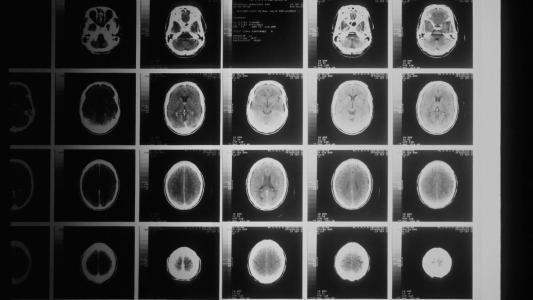

Brain mapping could one day allow us to create models of the brain’s structure and function.

Back in 2008, given the various technological bottlenecks to be overcome, discussions about WBE have assumed it was possible, but not in this century. Since then, many of the technical capabilities required for making progress, such as brain scanning and mapping technologies, have been rapidly improving. E11 for instance, is a new moon-shot effort to make brain mapping easier and more accessible. Data obtained from brain mapping could one day allow us to create models of the brain’s structure and function. These could then be used for developing algorithms that simulate neural activity — a first step on the path to WBE.